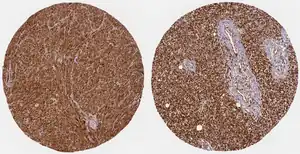

Medium intensity WWTR1 protein expression in melanoma samples from Protein Atlas.

WWTR1 protein is expressed in moderate to high levels across a diverse array of cancer types and is associated with poor clinical outcomes.